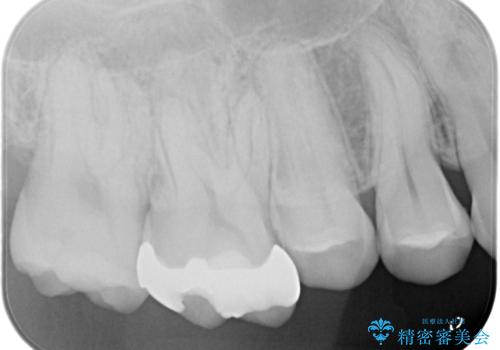

- 他院で歯の根っこの先端に膿が溜まっているため治療が必要だといわれた患者様です。

根っこの治療を顕微鏡を見ながら行ってくれる医院を探して当院に来院されました。

もともと症状はない状態でしたが、治療後は少しずつ病変の大きさが小さくなっているのを確認できます。

以前治療した際のむし歯が大きく、長い年月の間に少しずつ歯髄が死んでしまったと思われる状況でした。

長期にわたる炎症により、口蓋根尖は吸収を起こしていたため、MTAにて充填しています。